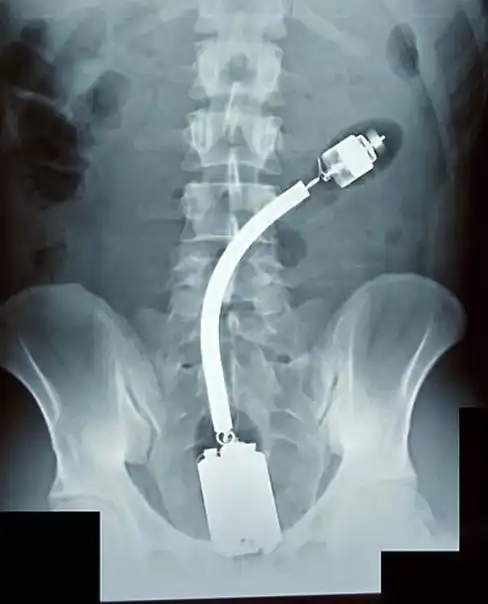

Огромный вибратор в заднице. Залез полностью. Без хирургического вмешательства достать не смогли.